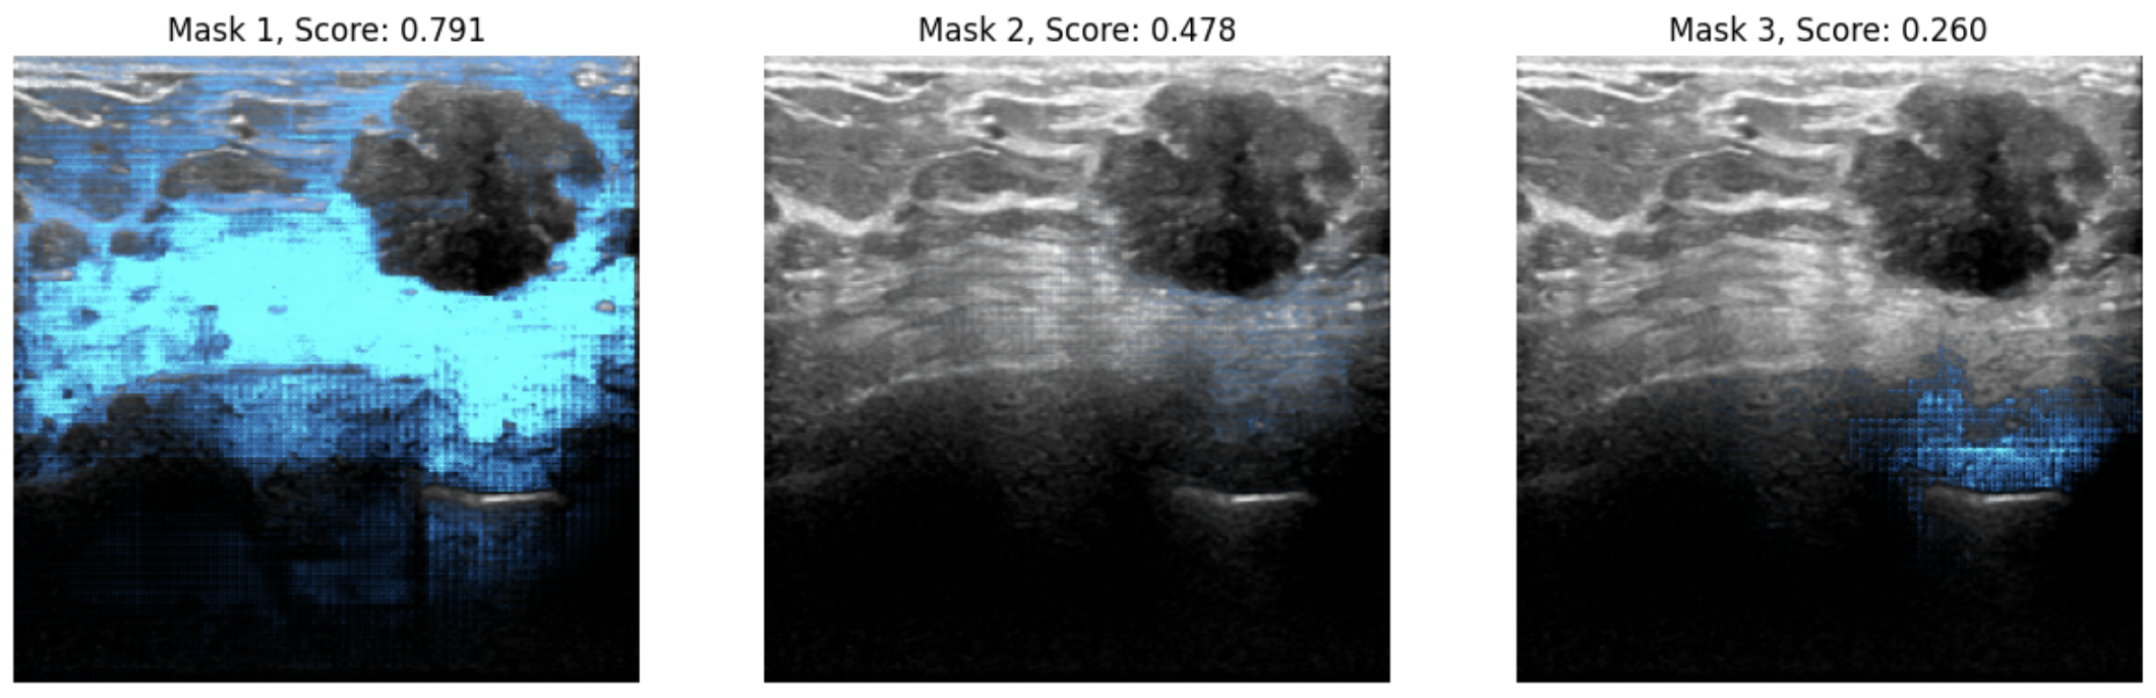

This model is a fine-tuned version of facebook/sam-vit-base on an breast cancer dataset. It is not trained for production but for Keras example.

You can see an example inference below.